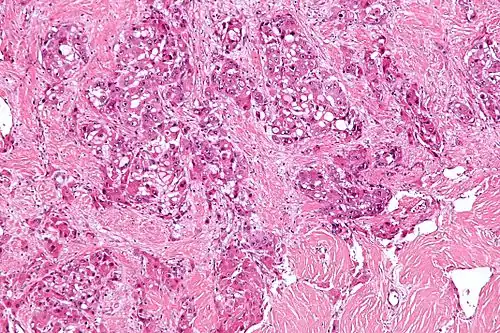

Micrograph of fibrolamellar hepatocarcinoma showing the characteristic laminated fibrosis between the tumor cells with a low NC ratio. H&E stain.

The histopathology of FLC is characterized by laminated fibrous layers, interspersed between the tumor cells. Cytologically, the tumor cells have a low nuclear to cytoplasmic ratio with abundant eosinophilic cytoplasm.[1] Tumors are non-encapsulated, but well circumscribed, when compared to conventional HCC (which typically has an invasive border).